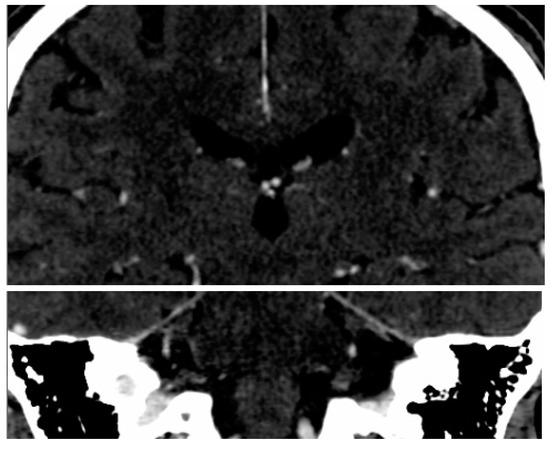

2.2. Imaging Protocol